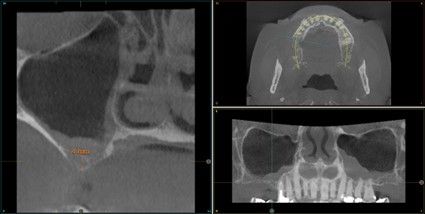

Resultados. Fueron reclutados 13 pacientes en los que se insertaron 30 implantes. Una vez insertados y cargados los implantes, la altura media final fue de 9,68 mm (+/- 2,66), lo que supone una ganancia promedio de 5 mm. A los 10 años, se observó una disminución media de la altura ósea ganada en los implantes en conjunto de 0, 29 mm (+/- 0,77). La media de la pérdida ósea mesial fue de 0,73 mm (+/- 0,75 mm) y la media de la pérdida ósea distal fue de 0,98 mm (+/- 1,2 mm). La supervivencia fue del 100%.

Results.Thirteen patients were recruited and 30 implants were inserted. Once the implants were inserted and loaded, the mean final height was 9.68 mm (+/- 2.66), which represents an average gain of 5 mm. At 10 years, there was a mean decrease in the overall bone height gain of the implants of 0.29 mm (+/- 0.77). The mean mesial bone loss was 0.73 mm (+/- 0.75 mm) and the mean distal bone loss was 0.98 mm (+/- 1.2 mm). Survival was 100%.

Los senos tratados con la técnica de elevación transcrestal sin material de relleno muestran un incremento de entre 2,5 mm12,13 hasta 4.4 mm14,15 en la altura ósea lograda sobre el ápice y una supervivencia de los implantes que se sitúa entre un 94 y un 100%16-17. En este trabajo se presenta un estudio retrospectivo donde se ha evaluado la inserción de implantes extracortos (5,5 y 6,5 mm) en zonas posteriores maxilares mediante la técnica de elevación de seno transcrestal con la fresa de ataque frontal sin la utilización de material de injerto, con un tiempo de seguimiento de 10 años para poder objetivar el comportamiento de los implantes a largo plazo y de la técnica empleada.